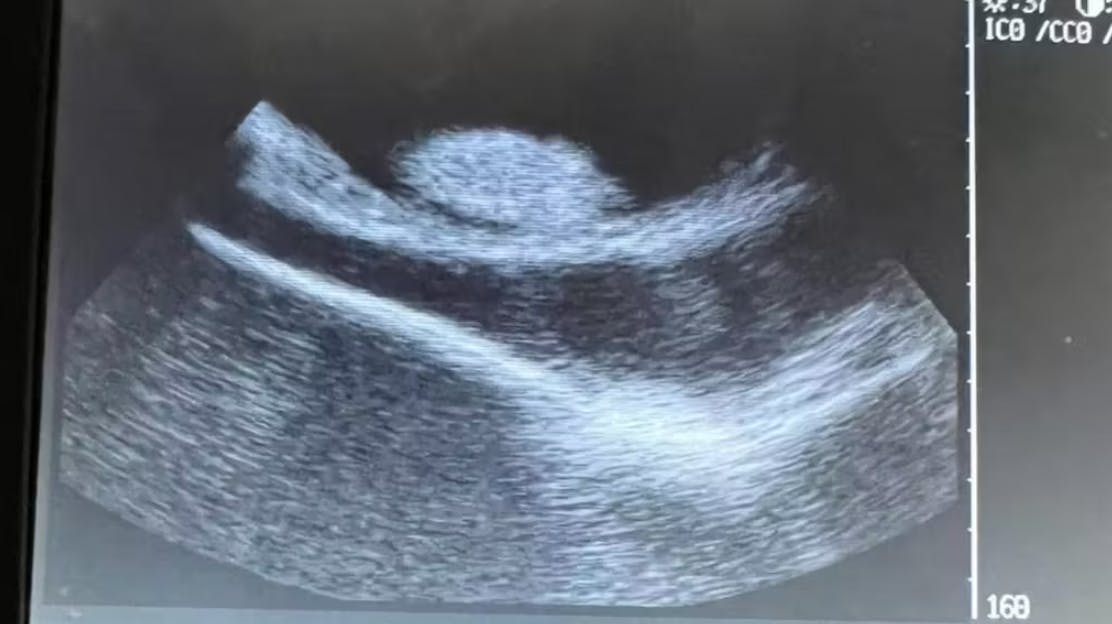

– Vi venter stadig tålmodigt på, at Charlotte føder. Den ultralydsscanning, som vi sendte til vores kolleger, ser god ud, og der var ingen tegn på mistrivsel. Vi vil dele nyeste nyt, efterhånden som det sker. Det har været en fantastisk rejse, og vi takker jer for at følge med i den, skriver akvariet på sin instagramprofil.

Siden er hun så blevet ultralydsscannet ad flere omgange, og her har personalet kunne se med egne øjne, at der altså ”svømmer” tre til fire små unger rundt inde i hendes mave.